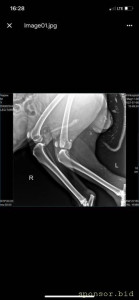

рентген

Помощь сбитой собачке - рентген 6.jpeg

Помощь сбитой собачке - рентген 1.jpeg

Помощь сбитой собачке - рентген 2.jpeg

Помощь сбитой собачке - рентген 3.jpeg

Помощь сбитой собачке - рентген 4.jpeg

Помощь сбитой собачке - рентген 5.jpeg

08.07.2022 г. передо мной на Варшавском шоссе сбили собаку, человек совершивший наезд даже не остановился и укатил дальше, я выбежала из машины, смогла остановить движение пары соседних полос, чтобы пес мог отползти на траву ( поднять и перенести не представлялось возможным, т.к. мне нельзя поднимать более 2 кг, более того непонятно что могла сделать собака в состоянии стресса и шока), после чего нашла парковку для машины и побежала к собаке, благо на тот момент несколько неравнодушных людей уже окружили его (это мальчик). Нами была вызвана полиция, составлено заявление ( но, думаем вряд ли кто-то будет этим заниматься.. так же сделан запрос в московскую службу видеофиксации, чтобы был сделан архив видео, если там есть камеры (тогда было не до этого, чтобы рассматривать есть ли они там), и в последствии приобщить к делу, или хотя бы найти того козла). Договорились со службой отлова, чтобы они на своей газели помогли довезти собаку до клиники шанс био, т.к. непонятно было что у нее с лапами, в клинике сделали рентген, несколько капельниц, обработали рану (т.к. задняя лапа разодрана до кости), взяли анализы, вкололи обезболивающие и отпустили.. т.к. у них нет стационара для бездомных, а так же хирурга, который мог бы сделать операцию. по заключению - кровоизлияние в глаз, открытая рана на левой заплюсне, вывих левого тбс (но вправить его нельзя, нужно делать операцию) порваны связки. по сумме в клинике оставили 14 500 руб. далее собаку отвезли в стационар надежда, с пятницы по воскресенье - обошлось в 10 552 руб (сам стационар, плюс лекарства, уколы и обработка ран, консервы, но он не ел). сегодня собаку возили на консультацию к хирургу в клинику беланта, было сделано дополнительно узи, на данный момент необходимо стабилизировать собаку, т.к. она еще в состоянии шока и с пятницы даже не ела, сейчас его опять повезли в стационар, необходимо еще делать уколы и обрабатывать рану, так же необходимо сделать 2 операции: на бедро (27200) и колено(55000), чтобы он смог передвигаться. в клинике заплатили 8167 с учетом лекарств. завтра планируется прием е еще одному хирургу в добрые руки, там по телефону озвучили цены на операции ниже чем в беланте, но нужен осмотр хирурга и его заключение. итого на данный момент на собачку ушло 33 219 руб. просим в сложившейся ситуации финансово помочь в судьбе пса, возможно найти ему любящих хозяев, на улицу его выкинуть уже просто невозможно, он там погибнет.. пес безумно умный, терпеливый, добрый, за все время ни разу не пытался агрессировать, укусить или что-то еще..